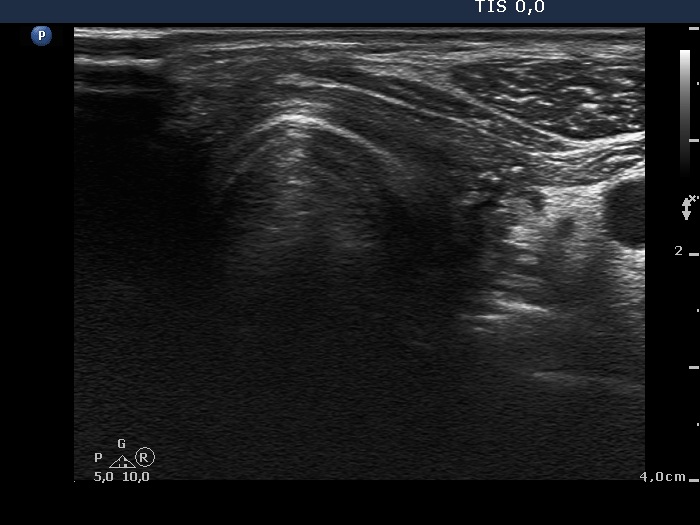

The operated thyroid - case 710

Four months after surgery (ultrasonographic picture 5)

Lower part of the left thyroid bed, transverse scan.